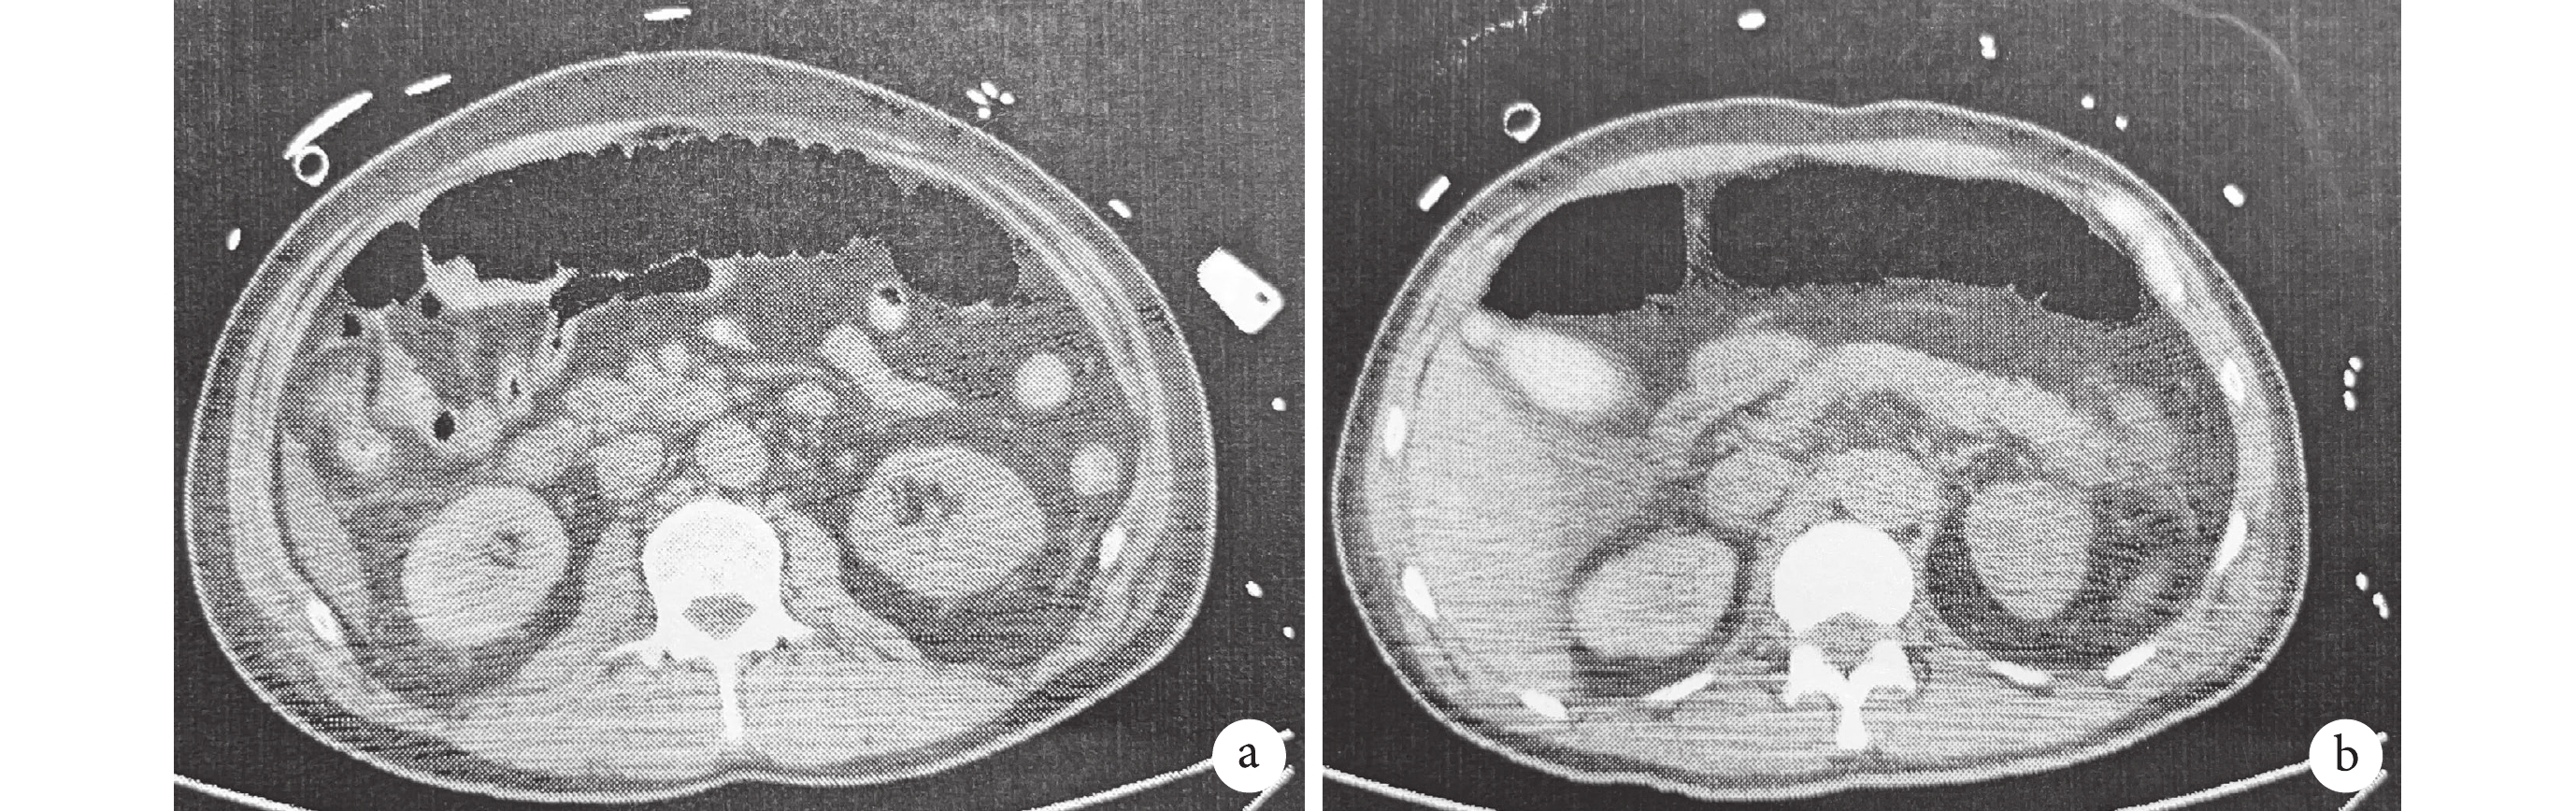

3例(16.67%)術前存在腸系膜上動脈夾層的患者(2例雙腔供血,1例假腔供血),術后2例患者腸系膜上動脈恢復真腔供血,其中1例術后發生結腸破裂行腸部分切除術,腹部增強CT顯示其腸系膜上動脈通暢,腸系膜下動脈缺血;另1例因合并低心排血量綜合癥等而保守治療,后因感染、多器官衰竭死亡。1例術后腹部CT平片示橫結腸大量積氣(圖1),考慮腸系膜上動脈閉塞,后行DSA下支架植入術,此患者術后因嚴重的右心功能障礙行ECMO支持,后死于多器官功能衰竭。此3例患者消化道出血發生在術后第7~33 d;見表5。

患者術前腸系膜上動脈為雙腔供血,術后發生AMI時橫結腸積氣